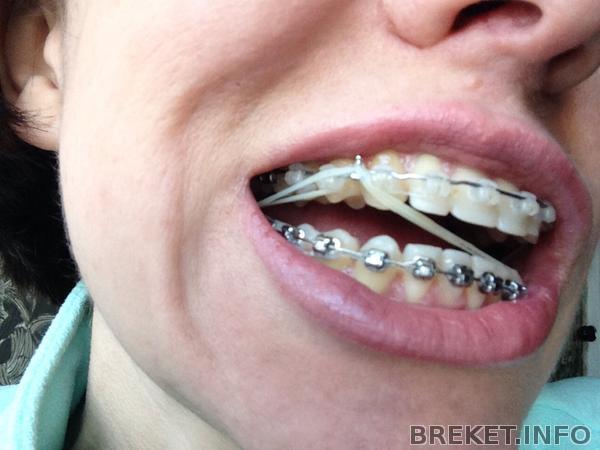

Тем временем клыки совсем придвинулись к пятеркам, а улыбка в данный момент выглядит, мягко говоря, отвратительно

и Бог с ними с щелями, но верхние зубы опускаются все ниже, уже совсем закрывают нижние - из-за чего, когда я улыбаюсь, очень сильно видно десну, что уж говорить о том, когда смеюсь((( Начала снова ненавидеть свои фотографии из-за этого и вообще в полном расстройстве